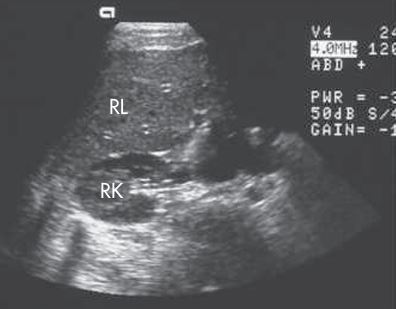

SAG of liver/kidney interface

TRANS - lobe and kidney

TRANS - RT kidney, GB, and Liver